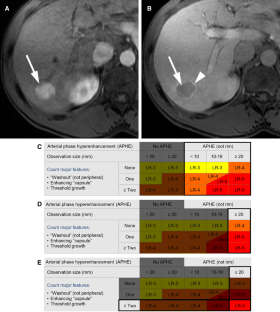

LI-RADS® algorithm: CT and MRI

The Liver Imaging Reporting and Data System (LI-RADS®) is an imaging-based diagnostic system applicable in patients at high risk of hepatocellular carcinoma (HCC). In LI-RADS, each liver observation is assigned a category that reflects probability of benignity, HCC, or other malignancy. Familiarity with the LI-RADS diagnostic algorithm is necessary to appropriately implement LI-RADS in clinical practice. This review discusses steps necessary for application of the LI-RADS algorithm and provides examples illustrating each step.